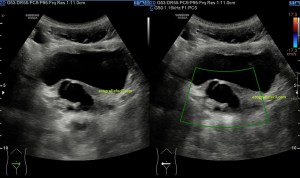

Aquí en la imagen 6 te muestro como es el tendón, sus dos porciones, según la afectación, donde puedes ver sus fibras conservadas (proximales) y afectas (distales). La afectas, heterogéneas, el tendón aquí aumenta su tamaño, por el edema, no pierdas detalle del retináculo, engrosad justo donde el tendón varía de ecogenicidad.

La membrana sinovial o vaina tendinosa (gracias María) está aumentada en su tamaño por el líquido que contiene, líquido denso, ecogénico, que rodea el tendón en este caso. Imagen 7.